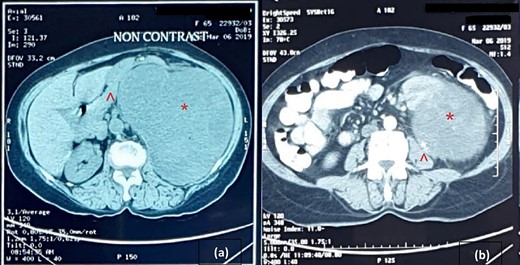

An abdominal ultrasound (US) revealed a 12 × 12 cm solid mass from the left suprarenal area (Fig. 1). Contrasted computed tomography (CT) revealed a 17.5 × 11.5 cm enhancing lesion in the left suprarenal region, completely replacing the left adrenal gland. The left kidney was inferiorly displaced, and coarse calcification was seen at the lesion’s periphery without lymph node enlargement. The contralateral adrenal gland, retroperitoneal and peritoneal structures were normal (Figs 2 and 3). Screening for primary carcinomas presenting as adrenal deposits utilizing clinical examination, pan endoscopy and contrasted CT were all negative. At this point, our working diagnosis was non-secreting left pheochromocytoma, and elective laparoscopic left adrenalectomy was planned.

CT image: (a) coronal section and (b) sagittal section; the red asterisk mark in (a, b) shows the tumour and the red arrowhead in (a, b) shows the inferiorly displaced left kidney.

Cross-sectional image of computer tomogram; (a) non-contrasted image and (b) contrasted image; the red asterisk mark in (a, b) shows the tumour, the red arrowhead in (a) shows anteriorly displaced pancreas and the red arrowhead in (b) shows the clear distinction of tumour from the left psoas.